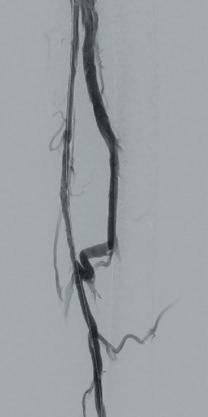

Arteriogram, left lower extremity

An arteriogram of the left lower extremity was performed via antegrade left common femoral artery access based on preoperative review of the lower extremity arteriogram from Uzbekistan. Scattered non-calcified plaque with moderate to high-grade stenoses were identified in the proximal and mid superficial femoral artery. Diffuse severe calcified tibial artery disease was identified. There was a long segment stenosis of the proximal and mid posterior tibial artery coupled with a more distal occlusion. The proximal peroneal artery was calcified and occluded with distal reconstitution identified. There was complete occlusion of the anterior tibial artery (Figure 2).